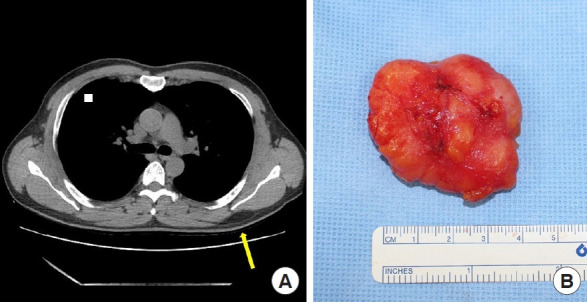

Methods: We retrospectively reviewed 190 lipoma cases treated at a single medical center from January 2013 to August 2023. The accuracy of preoperative imaging techniques-ultrasonography (USG), computed tomography (CT), and magnetic resonance imaging (MRI)-in predicting lipoma depth was assessed.

Results: USG, CT, and MRI showed accuracies of 72.5%, 56.5%, and 79.3%, respectively, with MRI showing the highest predictive accuracy. The trunk was the most common site for lipomas (49.5%), followed by the upper (20.5%) and lower extremities (13.2%). USG was more accurate for lipomas in the lower extremities and neck, whereas CT was less accurate for lipomas in the trunk.

Conclusion: MRI is preferable for the preoperative depth assessment of lipomas, especially those located in the trunk. Accurate imaging is essential for guiding surgical planning and avoiding complications. Further studies with larger sample sizes are required to validate our findings.